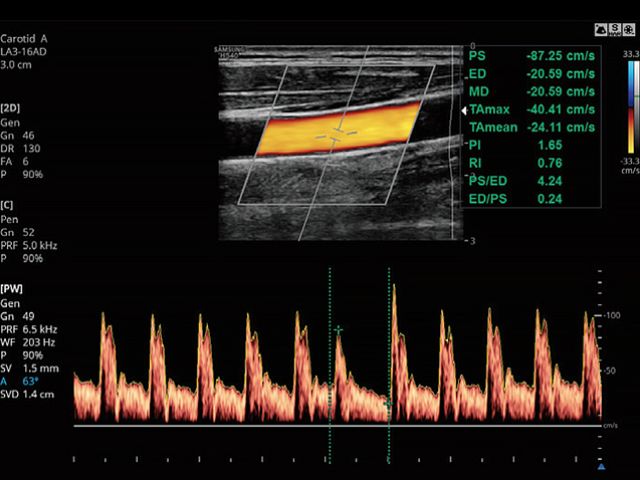

AutoIMT+ is a screening tool to analyze a patient's potential risk of cardiovascular disease. It allows easy intima-media thickness measurement of both the anterior and posterior wall of the common carotid by the click of a button.